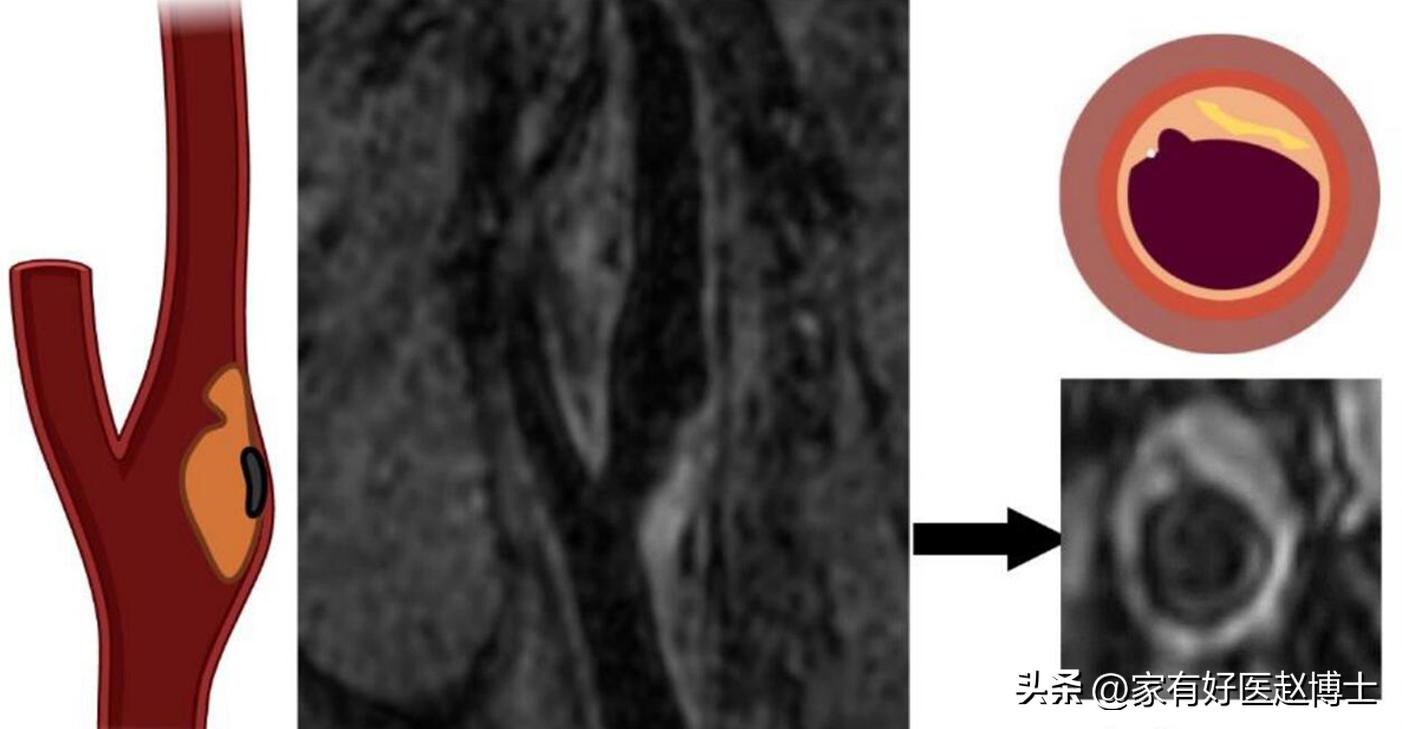

事实上,有一些斑块的体积并不大、也尚未造成血管的严重狭窄,但由于它们很“不稳定”,属于容易发生破溃的【易损斑块】,因此,其破坏力远超大家想象。

一旦这些易损斑块发生破溃,血液中的血小板会迅速聚集在此处,在很短的时间内形成足以堵塞整个血管的血栓。假如这些血栓被冲散,则会被血流带入大脑动脉,从而直接引起脑梗塞。

所以,当超声检查发现颈动脉斑块表现出某些“不稳定”的特征时(溃疡斑块、无/低回声斑块、管腔旁暗区面积、新生血管、斑块内出血及微栓子等),这提示我们需要警惕!面对这类斑块,要么,我们得想办法让它缩小;要么,我们就得使它变得更加稳固!而他汀在促进【斑块稳固】方面,也很有价值。